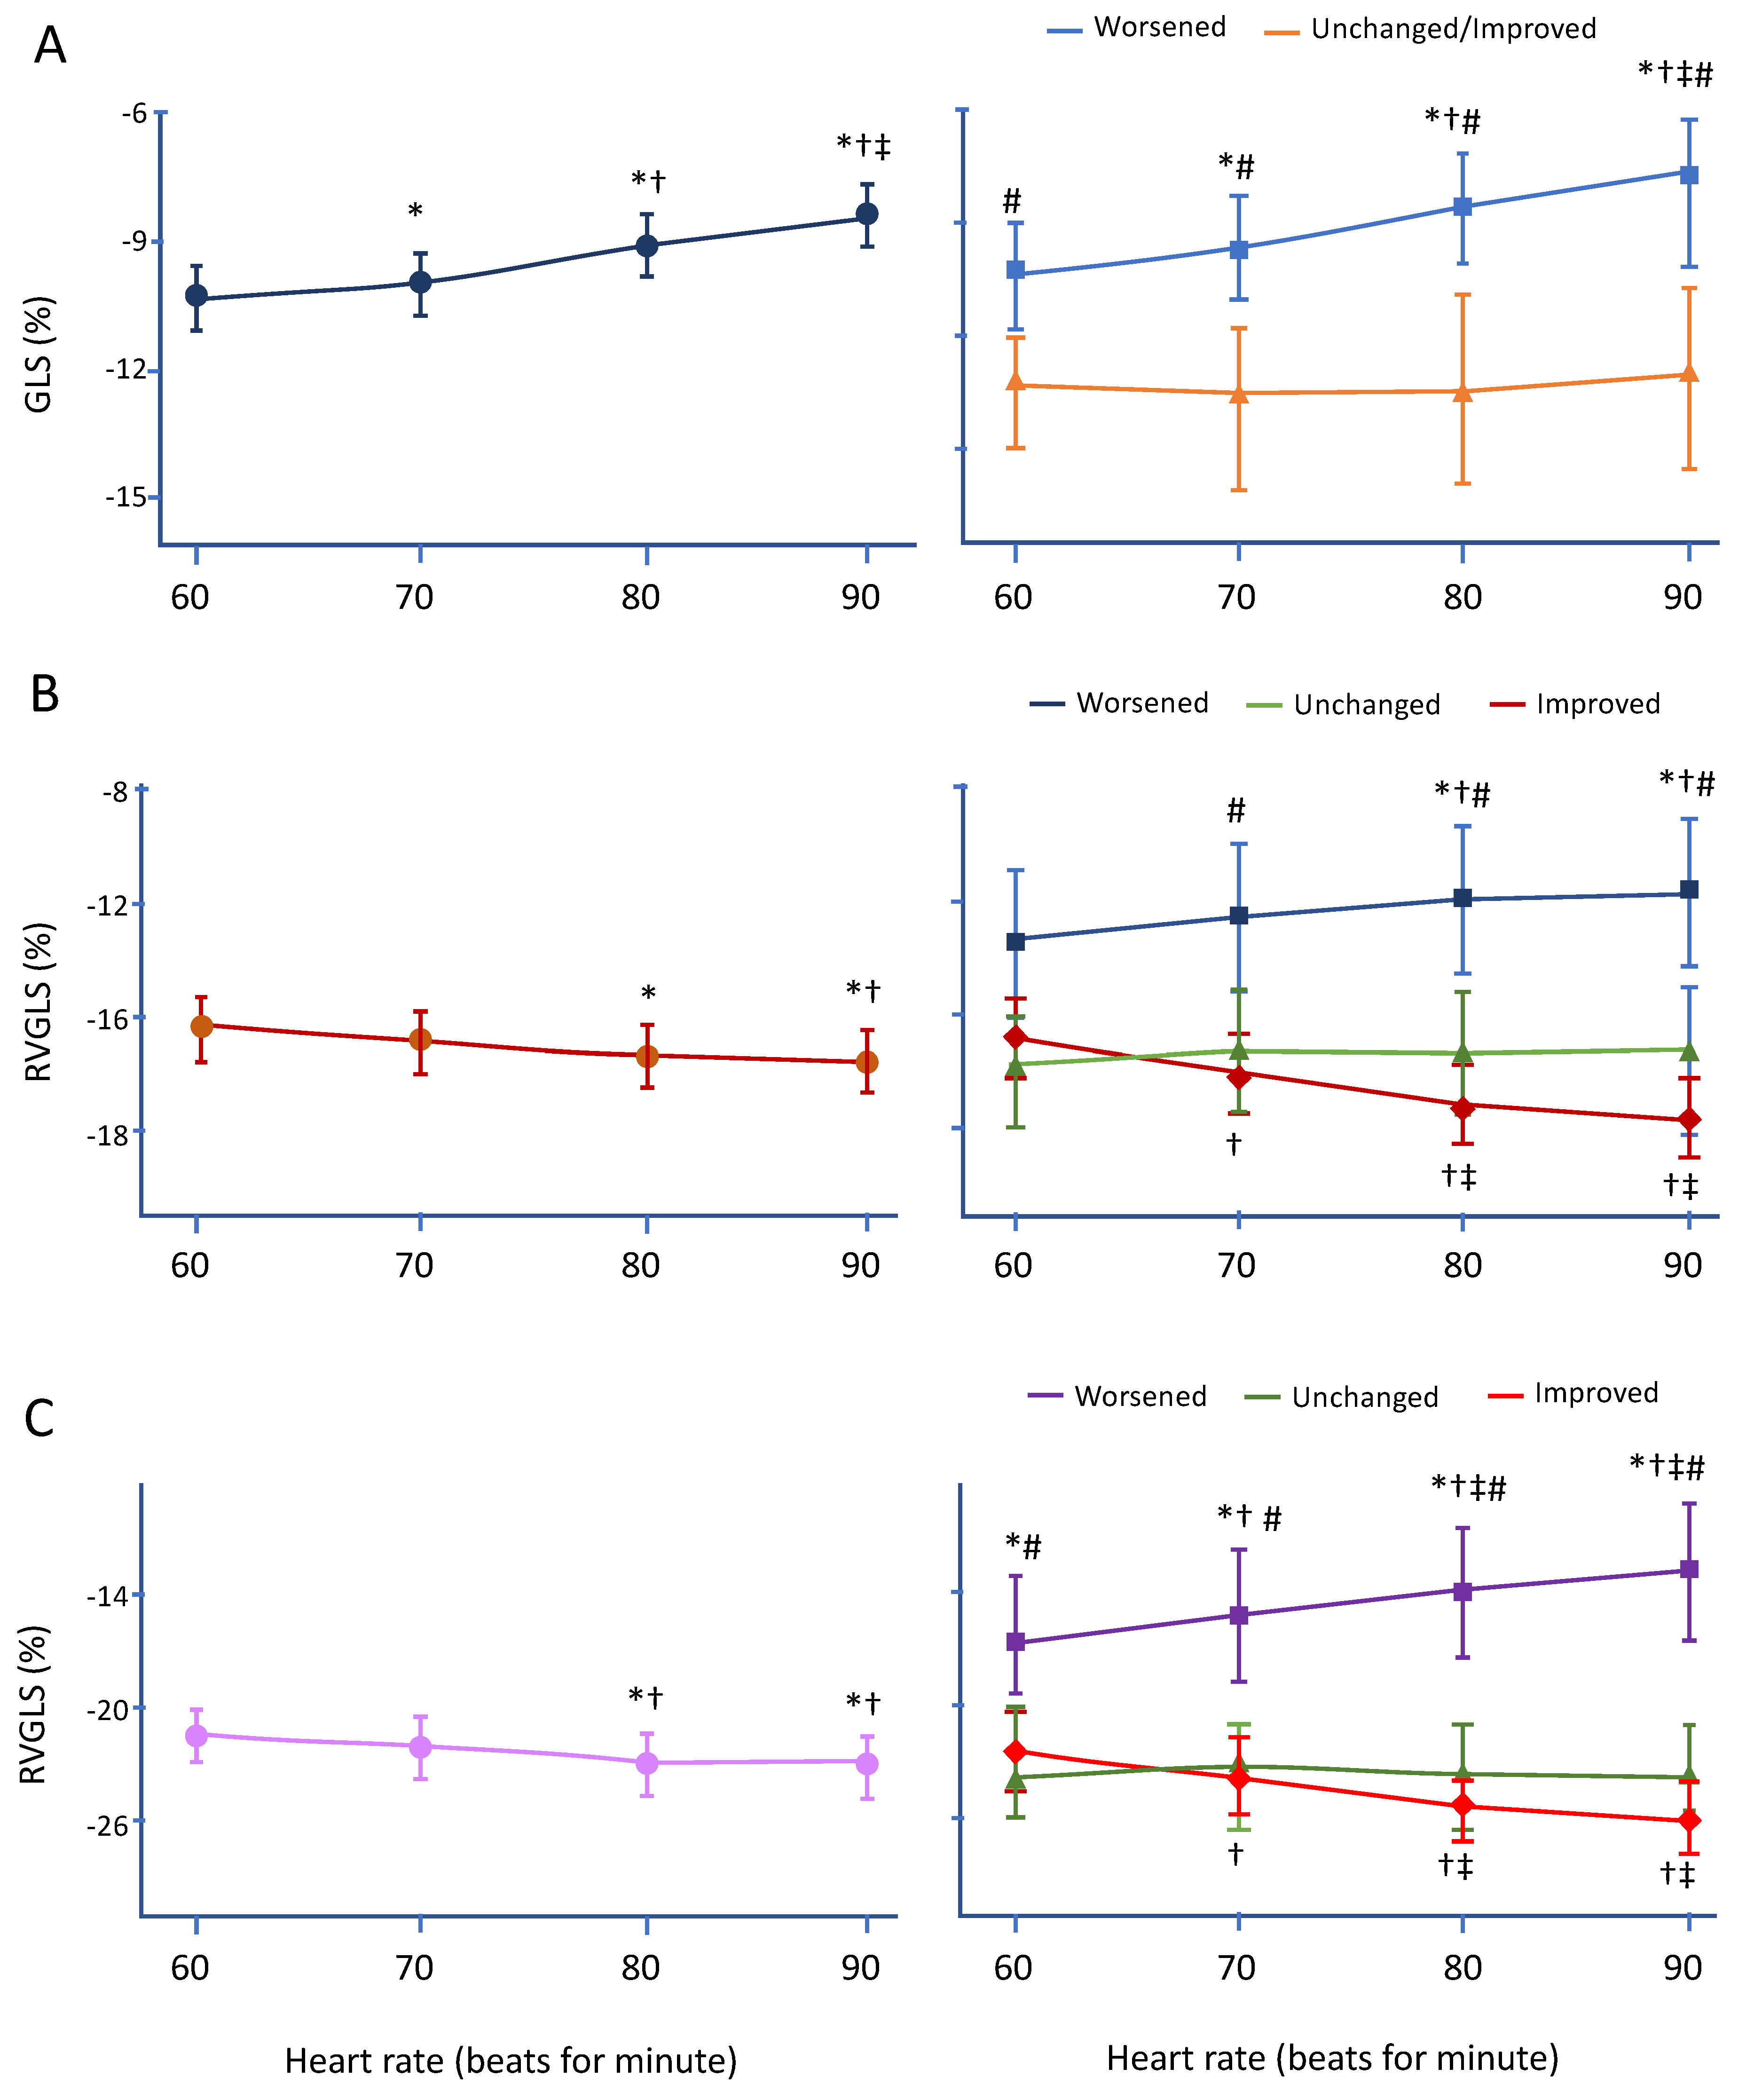

3.3. Changes in LVGLS during Pacing

3.4. Changes in RVGLS during Pacing

3.5. Changes in RVfwLS during Pacing